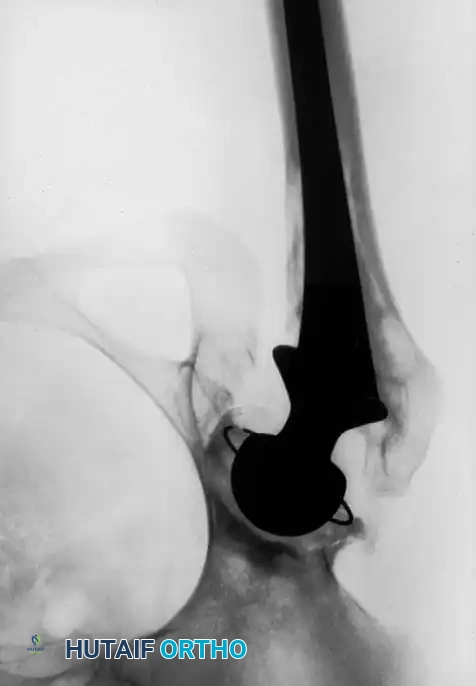

PROTRUSIO ACETABULI

Intrapelvic protrusio acetabuli is defined radiographically by the medial migration of the femoral head beyond the ilioischial (Kohler) line.

Fig. 7-74 Primary protrusio acetabuli. Otto pelvis in 52-year-old woman. Femoral head has migrated medial to ilioischial (Kohler) line. Hip motion is severely limited.

Principles of Reconstruction

The surgical management of protrusio acetabuli is technically demanding and relies on three non-negotiable biomechanical principles:

1. Restoration of the Anatomic Hip Center: The hip center of rotation must be lateralized and brought inferiorly to its true anatomic position to restore abductor mechanics and minimize joint reactive forces.

2. Peripheral Rim Fixation: The implant must be supported by the intact, structurally sound peripheral rim of the acetabulum, bypassing the deficient medial wall.

3. Medial Wall Reconstruction: Cavitary and segmental defects of the medial wall must be reconstituted, typically utilizing impaction bone grafting (autograft from the resected femoral head or allograft).

Fig. 7-75 Reconstruction for protrusio acetabuli deformity. A, Diagrammatic representation of medial wall grafting and lateralized cup placement.

Fig. 7-75 Reconstruction for protrusio acetabuli deformity. B, After total hip arthroplasty. Hip center was restored to more lateral and inferior position. Large acetabular component allowed rim fixation without need for screws, and medial deficits were grafted with cancellous autograft from femoral head with excellent incorporation.

Associated Surgical & Radiographic Imaging

Hutaifortho's Orthopaedic Diagram